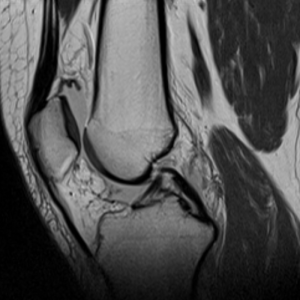

Olika pulsfrekvenser och ekointervall ger olika signal vid MR-undersökning. T1-viktning har hög pulsfrekvens och kort ekointervall, T2-viktning medel, PD (Proton Density) medel pulsfrekvens och kort ekointervall och FLAIR (Fluid Attenuated Inversion Recovery) låg pulsfrekvens och långt ekointervall. STIR (Short Tau Inversion Recovery) har extra högt pulsintervall.

| STIR | T1-viktning | PD | T2-viktning | FLAIR | |

|---|---|---|---|---|---|

| Fett | Mörkt | Ljust | Ljust | Ganska ljust | Ganska ljust |

| Vätska | Ljust | Mörkt | Ljust | Ljust | Mörkt |

| Inflammation | Ljust | Mörkt | Ljust | Ljust | Ljust |

| Skelett | Mörkt | Mörkt | Mörkt | Mörkt | Mörkt |

| Ryggmärg | Mörkgrått | Grått | Grått | Ljusgrått | Ljusgrått |

| Disk, menisk | Mörkt | Grått | Mörkt | Ljust | Grått |

| Muskel | Grått | Grått | Grått | ||

| Brosk | Mörkgrått | Grått | Mörkgrått |